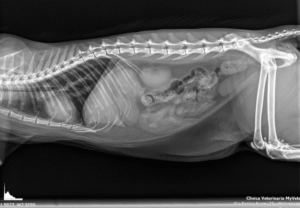

L’esame radiografico è uno step fondamentale nell’indagine diagnostica di base. La clinica è dotata di un apparecchio radiografico digitale diretto ad alta risoluzione che consente di ottenere immagini dettagliate e visualizzate istantaneamente, riducendo così il tempo di esecuzione dell’esame e risparmiando stress al pazienti.

Le imm agini vengono archiviate nel nostro database e possono essere trasmesse per via telematica.